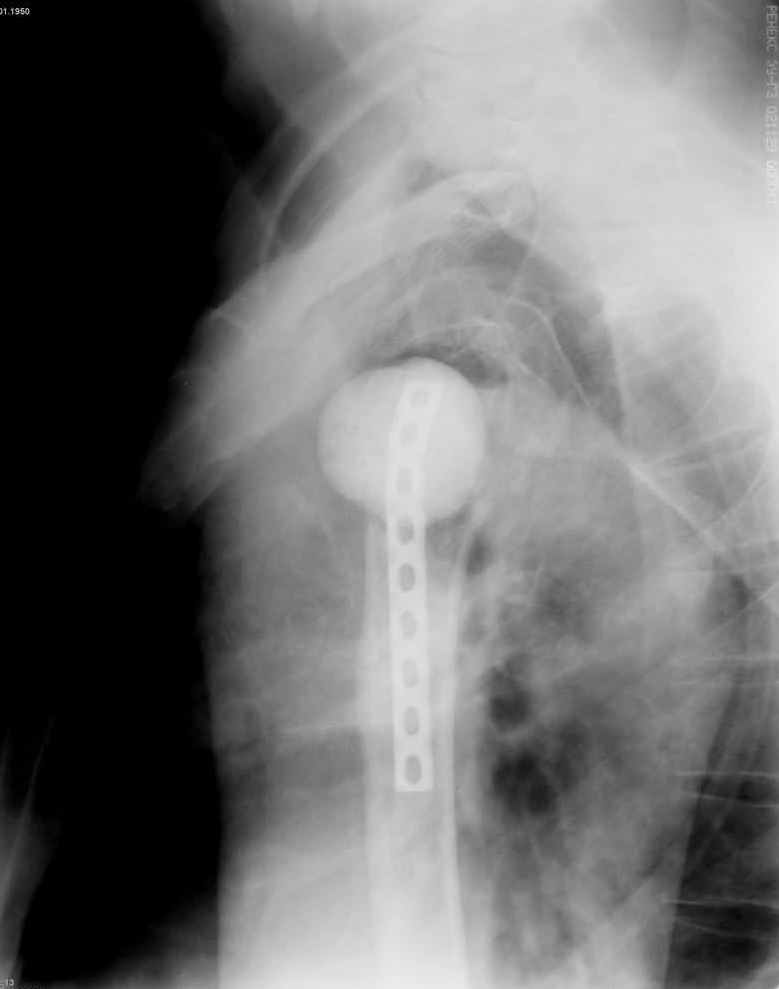

Уважаемые коллеги. Недавно из нашего отделения был выписан пациент 54 лет с закрытым переломом плечевой кости. Из анамнеза: за 2 дня до поступления в НИИСП, в состоянии алкогольного опьянения упал с лестницы на даче (высота 3-4 метра) с упором на правую руку. Через двое суток обратился за медицинской помощью. Доставлен бригадой "Скорой помощи".Правый плечевой сустав умеренно деформирован. По внутренней поверхности плеча имеется кровоподтек. При пальпации плечевого сустава имеется умеренная болезненность. Активные и пассивные движения болезненные. Снижена чувствительность по тыльной поверхности пальцев кисти и отсутствует активное разгибание кисти и пальцев. Имеется подкожная эмфизема шеи, верхней половины грудной клетки (рис 1, 2). На рентгенограмме: оскольчатый перелом головки плечевой кости со значительным смещением, перелом 2-3 ребер справа, тканевая эмфизема (рис 3). КТ при поступлении: перелом головки плечевой кости в области анатомической шейки со смещением отломка головки в грудную полость, правосторонний гидроторакс, перелом 2-3-4 ребер справа. (рис 4). Через двое суток после поступления выполнена операция: атипичная торакотомия, эвакуация свернувшегося гемоторакса, удаление инородного тела (головки плечевой кости) из плевральной полости (при этом выявлено имеющееся повреждение париетального и висцерального листков плевры) (рис. 5), дренирование плевральной полости, замещение проксимального конца плечевой кости спейсером из костного цемента с антибиотиком (рис. 6). Послеоперационный период протекал гладко. При контрольной рентгенографии положение спейсера удовлетворительное (рис. 7, 8). Дренаж из плевральной полости удален через 3 суток после вмешательства. Послеоперационная рана зажила первичным натяжением. Через 12 дней после операции больной выписан на амбулаторное лечение.